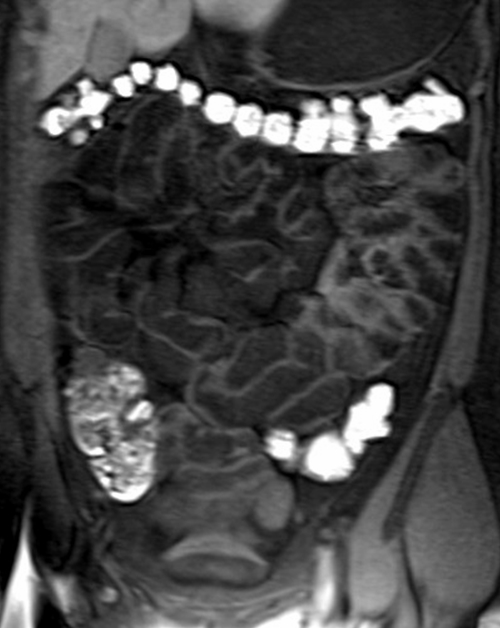

MRI small bowel (entrography) coronal flash pre contrast images

mri samall bowel coronal t1 flash image